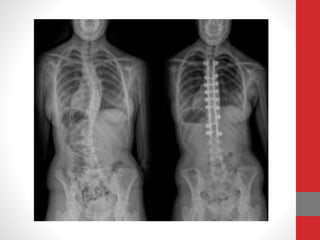

• Radiografia ( Raio X)

Diagnóstico • Radiografia (Raio X) • Testes Clinicos • Avaliação postural • Método de Cobb (Mensuração)